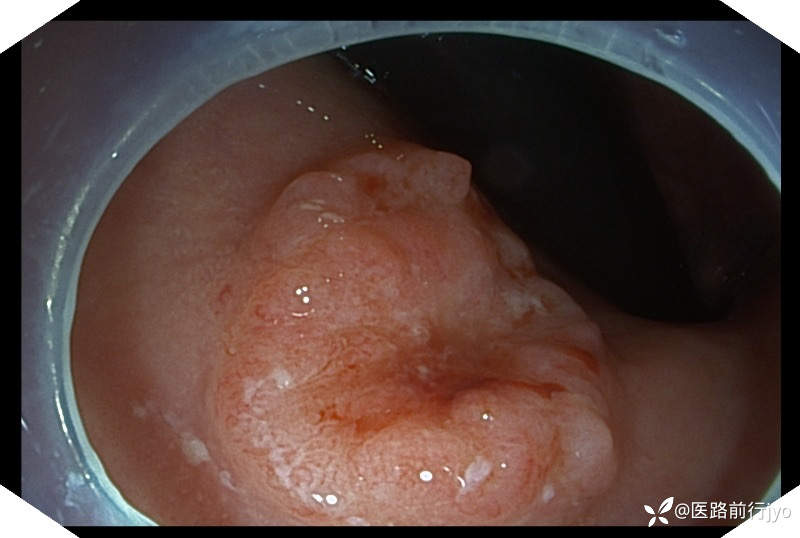

今日上午一例肠镜:患者 女 67岁 患者肠道清洁好,乙状结肠仅发现1枚小息肉,本准备退镜收工,退镜到肛门口突然看到一隆起性小片粘膜,立即倒镜观察考虑直肠早期癌变,距肛周约1cm的大小约1.6cmx1.3cm椭圆形欠规则隆起,中央凹陷伴自发性出血,活捡5块,质脆,易出血。考虑诊断:直肠粘膜不规则(11a+11c)隆起(考虑直肠癌可能)